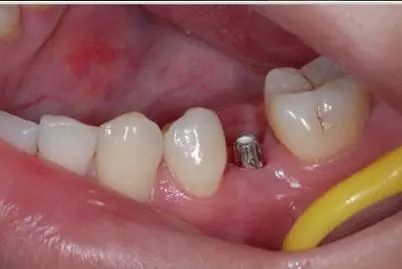

想一下啦,真係假牙可以同健康牙齒比嗎?假牙再好囉,食野感覺有啲唔舒服。除非你嘅牙齒全部爛哂,冇得補返,嗰陣醫生先會建議你拔牙。其實最貴係咩鑲牙,每顆假牙都係金錢!

至於鑲牙就更貴啦!植牙一粒都差唔多一萬啦!